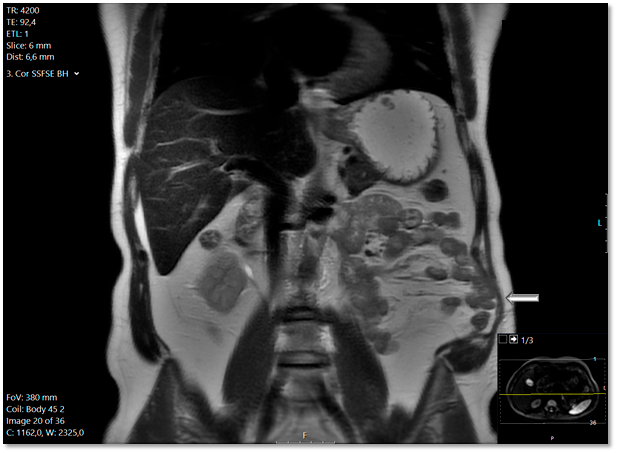

Die Narbenhernie wurde von dem Radiologen erst elf Monate nach der Nephrektomie diagnostiziert. Der Radiologe räumte nunmehr in seinem Befundbericht ein, dass diese sich auch schon in der Voruntersuchung andeutete – siehe Abbildung 1. Sie wurde einen Monat später laparoskopisch mit Einbringung eines Netzes versorgt. Postoperativ gab der Patient weiter erhebliche Beschwerden an: „im Stehen deutliche Vorwölbung linke Flanke/laterale Bauchwand, im Stehen und Liegen keine Bruchpforte tastbar. Befund auch wie bei Relaxatio der Bauchwand.“ Es folgten zahlreiche Konsultationen bei verschiedensten Chirurgen und Neurologen – allesamt nicht mit dem gewünschten Erfolg aus Sicht des Patienten.

Der „fehlende Befund“ ist in der Bildgebung 1 vorhanden, wird jedoch eben nicht kommuniziert und damit übersehen. Dies stellt mit 42 % die höchste Fehlerklassifikation in der diagnostischen Radiologie dar.1